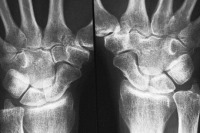

غضروف بافتی مهم در حد فاصل استخوانهاست که امکان حرکت اندامها در جهتهای مختلف را می دهد.

بررسیهای صورت گرفته نشان می دهد که می توان از این نوآوری برای جایگزین سازی بافت غضروفی آسیب دیده در ناحیه ران و زانو استفاده کرد.